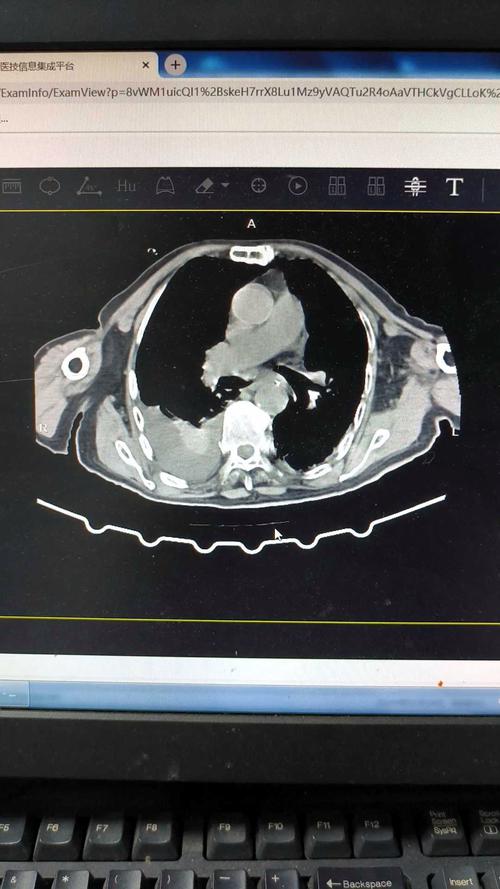

肺GGO,普通CT、HRCT常规扫描,难以去准确评价它,常有漏诊、误诊发生,怎么办?

谢谢你的邀请,先普及一下肺GGO及肺GGN定义,通俗的讲肺GGO就是肺内的磨玻璃密度影,肺GGN为肺内磨玻璃结节,大众通常所说的应该是磨玻璃结节。

第一针对GGN的发现,首选低剂量高分辨CT平扫,但是由于我国医疗水平分布不均匀,很多地区及部分县级镇无相应CT设备,无法重建出薄层CT图像,直径大于5毫米的结节一般有经验的正规放射科医生都应该能看到,并体现在报告上,但是对于小于5mm的结节,尤其GGN往往会漏诊,这是个客观的事实,针对这些地区人群,尤其是符合我国肺癌高危人群,换是建议就近到有相应CT设备的医院每年体检一次。

第二说到漏诊,确实每个医院医生水平又高有低,阅片能力也是如此,有些小于5毫米的纯磨玻璃结节,确实不容易观察,对于这种情况,换是建议多多复诊,这个复诊不是从新做一次CT,而是有电子版胶片或云胶片时,可以让其他医生会诊,减少漏诊可能。对于有条件的医院,还是建议实施云胶片,这是未来的趋势,无胶片化,二维码一扫电子胶片在手机上就是可以阅读,原始数据真实可靠,便于储存及便于调阅。

第三当我们发现GGN后,我们医生应该怎样客观对待它,而不至于误诊,患者怎样对待它而不至于恐慌。这又谈到肺结节话题了,我们这次只聊GGN,它又分纯磨玻璃结节PGGN和混合性磨玻璃结节mGGN, 混合性的往往恶性的可能性又大点,碰到这种结节,我们一般有经验的放射科医生或临床医生,结合患者临床病史及影像学变现,都能判断个八九不离十,对于可疑恶性结节,也行只有很牛的专家才能判断,往往很牛专家号都很难挂,这时常规就是处理原则就是短期随访,同时可以结合临床辅助抗炎治疗,短期随访复查,观察结节的变化再定其性质。最后我们放射科及临床都不怀疑的结节,那就常规半年或一年随访,对于这种结节,你完全没有必要恐慌,就算恐慌,你也无能为力,基本上所有医生都说不像是恶性的,随访吧,那我们就安心的随访吧,不然我们还能做些什么呢?